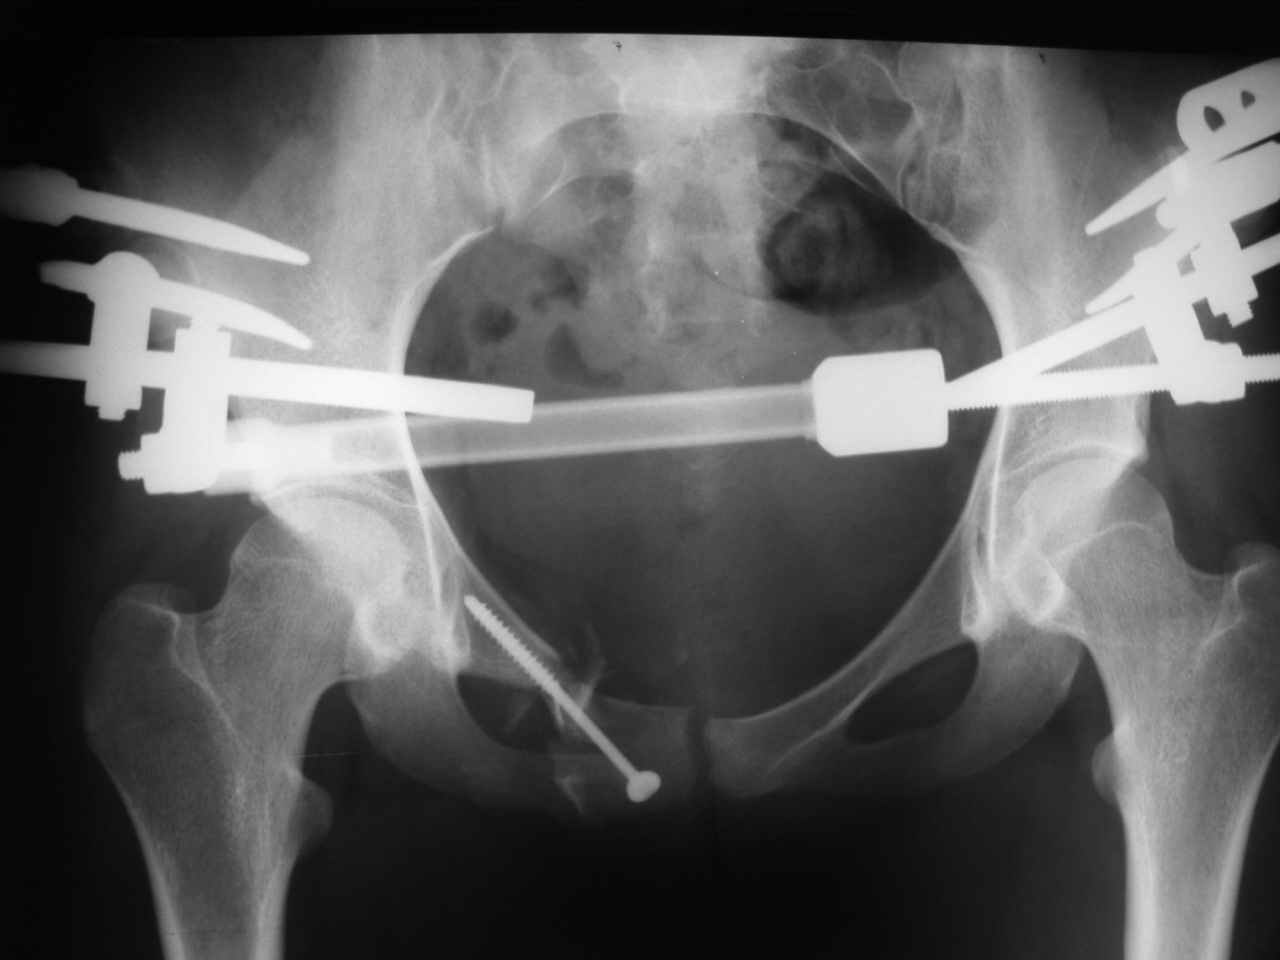

Re: Застарелый перелом лонной кости

Вот на этом думаю и остановится. А надо ли вообще фиксировать ротационное повреждение задних отделов винтами (тем более через месяц)? Было бы вертикальное, то тут без вопросов!